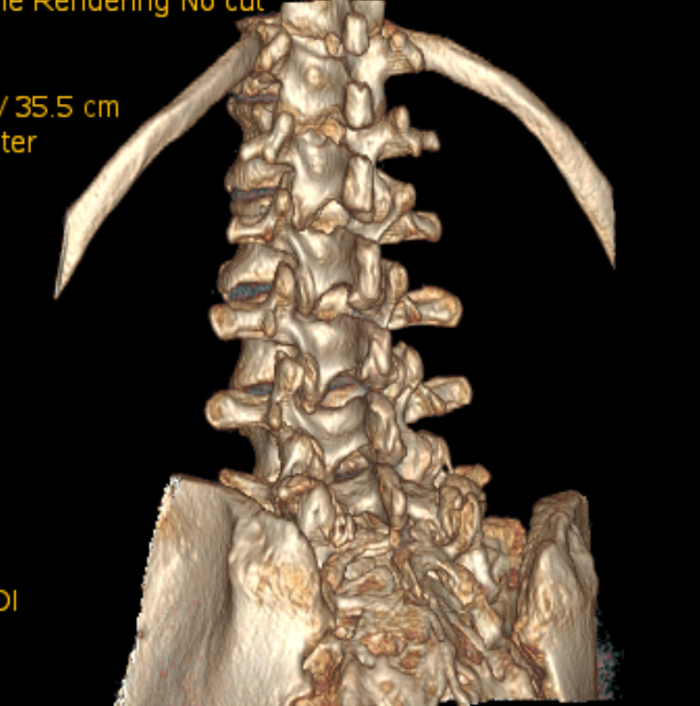

另外,由于巨大骶管囊肿的长期压迫,患者的骶骨已被广泛侵蚀破坏,无论是椎体还是椎板骨质都已大量损失,很多部位已经穿通。